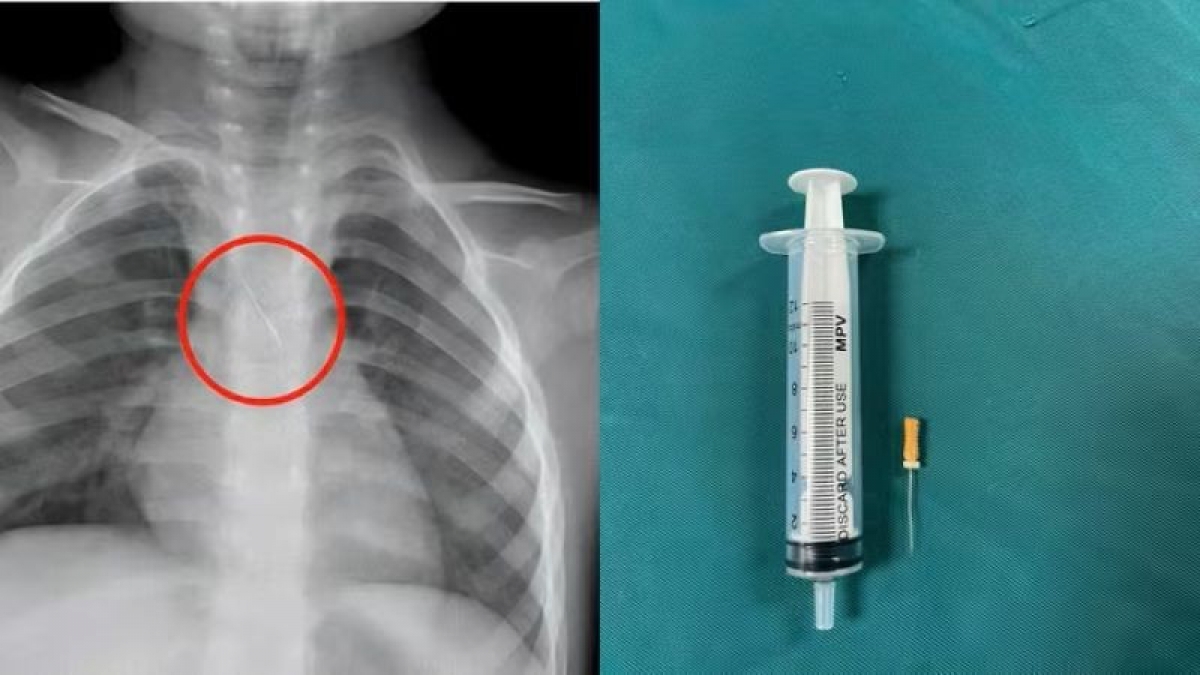

Kịp thời cứu cháu bé bị kim chọc tủy rơi vào đường thở

VOV1 - Bệnh viện Đa khoa tỉnh Quảng Trị cho biết, các bác sĩ vừa cấp cứu và gắp thành công dị vật trong đường thở cho bệnh nhi 3 tuổi trú tại xã Cửa Việt, Quảng Trị. Trước đó, bé nhập viện trong tình trạng ho nhiều, ho sặc.

# Bệnh viện Đa khoa tỉnh Quảng Trị cho biết, các bác sĩ vừa cấp cứu và gắp thành công dị vật trong đường thở cho bệnh nhi 3 tuổi trú tại xã Cửa Việt, Quảng Trị. Trước đó, bé nhập viện trong tình trạng ho nhiều, ho sặc. Qua thăm khám và chụp phim, các bác sĩ xác định bé bị sặc kim chọc tủy dài khoảng 22mm, vị trí mắc tại góc carina, nơi chia đôi khí quản. Đây được đánh giá là ca cấp cứu nguy hiểm. Bệnh viện kích hoạt hội chẩn liên khoa và quyết định tiến hành nội soi phế quản cấp cứu. Dị vật được phát hiện với một đầu nhọn cắm vào đoạn dưới khí quản, đầu còn lại nằm trong phế quản gốc trái. Sau khoảng 15 phút xử trí, các bác sĩ lấy thành công dị vật. Bé cải thiện ngay triệu chứng, được theo dõi 48 giờ và xuất viện trong tình trạng ổn định.